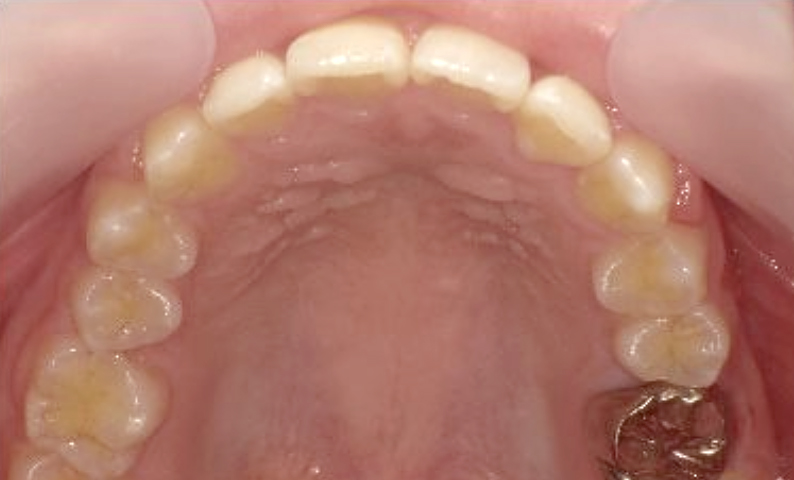

症例_001 上下顎の部分矯正

治療期間:12ヶ月金額:54万円+税女性前歯のガタガタ逆八の字